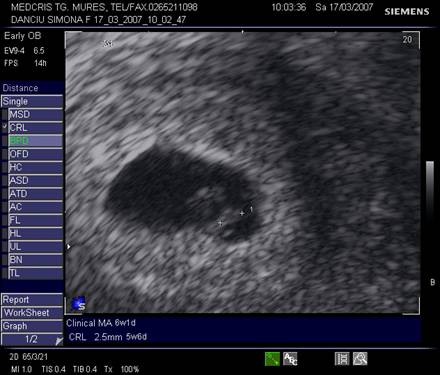

Fig. nr.104 Sarcina normala de 5 saptamani la ecografia transvaginala